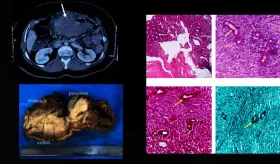

El diagnóstico correcto se estableció al cumplir los Criterios de Whipple y confirmarse un hiperinsulinismo endógeno mediante una prueba de ayuno y estudios de imagen que localizaron un tumor neuroendocrino en el páncreas.

Las imágenes sugerían infiltración linfomatosa, pero la esplenectomía ...